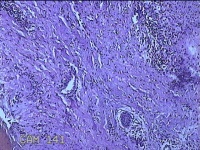

左侧会阴部结节

性别

女

年龄

43岁

临床诊断

皮肤良性肿瘤

一般病史

发现右侧会阴部结节3年余。

标本名称

大体所见

灰白粉红色带皮肤结节0.8x0.7x0.3cm一个,表面光滑,切开结节呈实性,切面灰白粉红色,质韧。